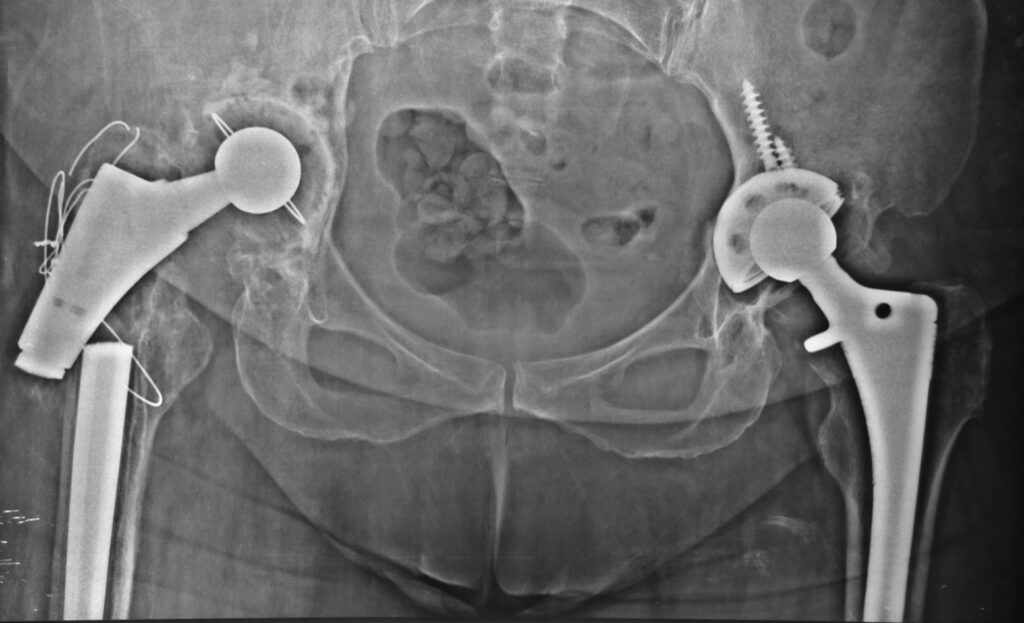

Αλλαγή της ευθυγράμμισης της άρθρωσης ή εξάρθρωση (ιδίως στο ισχίο)

Αφαίρεση της παλιάς πρόθεσης

Καθαρισμό των ιστών από τυχόν μόλυνση ή ουλώδη ιστό

Ανακατασκευή του οστού (αν υπάρχει οστική απώλεια)

Τοποθέτηση νέας πρόθεσης, ειδικά σχεδιασμένης για αναθεωρήσεις

Οι προθέσεις αναθεώρησης είναι πιο σταθερές, μακρύτερες και συχνά συνδυάζονται με μοσχεύματα ή μεταλλικά ενθέματα.